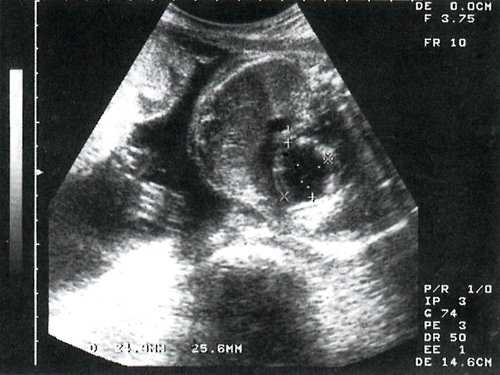

При скрининговом исследовании в 3 наблюдениях у молодых первобеременных при минимальном сроке гестации 24 недели выявлены одинаковые изменения сердца плода. Отмечалось значительное увеличение размеров сердца за счет левого желудочка с шарообразной его конфигурацией. Верхушка сердца полностью сформирована левым желудочком. Миокард левого желудочка утолщен и полость сферически расширена, при этом межжелудочковая перегородка выпячивается в полость правого желудочка (рис. 1).

Рис. 1. Эндокардиальный фиброэластоз у плода в 26 недель гестации. Четырехкамерное сечение сердца плода.

Сосочковые мышцы также уплотнены. В качестве ультразвукового признака, который не отмечается ни при какой-либо другой аномалии сердца, было обращено внимание на признак "светящегося" эндокарда - плотного и блестящего, степень отражения от которого наблюдается и при незначительном уменьшении усиления ультразвукового луча.

Безусловно, антенатальная диагностика фиброэластоза основывается в значительной степени на нарушении сократимости миокарда и плотности эндокарда. По нашим данным, наиболее характерным является плотность эндокарда, достигающая нескольких миллиметров, эхопозитивность структуры эндокарда и "светящийся" эндокард (см. рис. 1). В зависимости от формы полость может быть расширена и представлять классический вариант патологии - неподвижные стенки, блестящий плотный эндокард и выпячивание межжелудочковой перегородки в сторону правого желудочка, т.е. шарообразная форма левого желудочка.